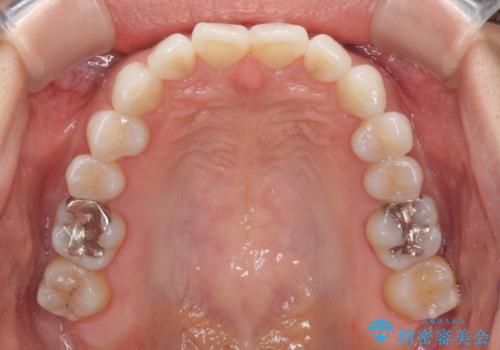

- 前歯のデコボコを気にして来院された患者様です。

歯列不正が軽度であり、インビザラインの装着時間を遵守してくださったため、日本と海外を行き来しながらも2年弱でしっかりと仕上げることができました。